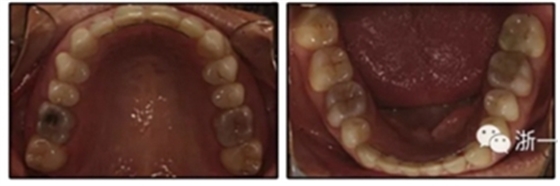

患者是一名39歲的白人婦女,病史不明。她主訴是她的右側(cè)顳下關節(jié)有不適癥狀,并希望改善她的笑容。她有一個對稱的臉型和一個II類2分類的微笑。她的側(cè)貌是凸的,90°的鼻唇角和骨性下頜骨發(fā)育不足??趦?nèi),上頜中線與面部重合,但下頜中線向右側(cè)偏移5mm;存在6mm的深覆蓋。她的兩側(cè)都是I類磨牙關系,左側(cè)是I類尖牙關系,右側(cè)是完全的II類尖牙關系。下頜右側(cè)第二前磨牙先天性缺失(圖1和圖2)。最初的全景片顯示了足夠的骨質(zhì)水平和全部的第三磨牙(圖3)。治療前的頭影測量片片和相應的頭影測量圖(圖3)證實ANB為7°,Wits評估為6 mm的骨性II類錯合(表)。上頜切牙相對與面部和顱底的位置很好。下頜切牙前傾。診斷為II類2分類錯合畸形,伴有骨性下頜發(fā)育不足,右側(cè)顳下頜關節(jié)癥狀,下頜中線向右側(cè)偏移5mm,先天性右下第二前磨牙缺失。

圖2. 治療前牙齒石膏模型

患者決定采用非手術治療方法,側(cè)貌沒有任何預期的變化。治療后面部照片(圖5)顯示她改善的微笑和側(cè)貌,包括尖牙保護合。由于先天性第一前磨牙缺失,右磨牙關系為III類。治療后牙齒石膏模型(圖6)顯示實體牙齒交錯排列情況,并且全景X線片顯示可接受的牙根平行度而且沒有牙根吸收表現(xiàn)(圖7)。最終的頭影測量片(圖7)證實了面部評估,并且描跡圖顯示深覆蓋的改善,同時保持上頜切牙位置并通過測量ANB角度和Wits評估改善骨性II級關系(表)。治療前后的疊加圖顯示由于下頜切牙前傾的增加改善了下唇平衡(圖8)。如相關治療計劃所預測的那樣,B點出現(xiàn)。A進行牙科錐形束計算機斷層掃描以記錄下頜前牙區(qū)的骨質(zhì)變化。如預期的那樣,由于治療導致該區(qū)域的骨量增加(圖9)。